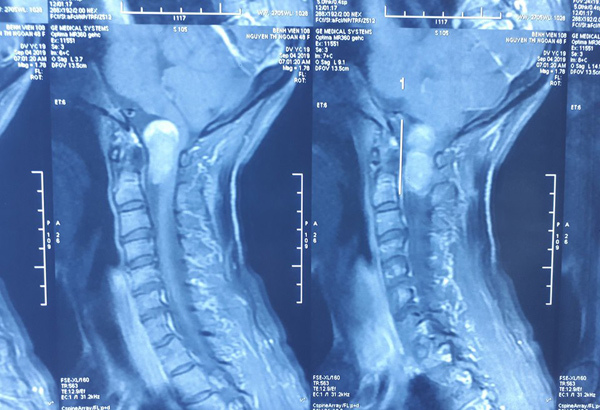

Đầu đau như điện giật, bác sĩ lấy ra ‘thủ phạm’ ở cổ

- Bà Năm thấy đau đầu liên tục không thể ngủ, nhiều lúc đau nhói như điện giật xen kẽ bỏng rát vùng đầu.